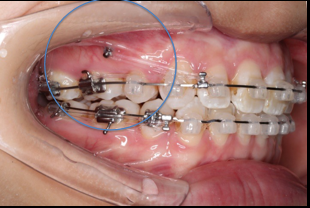

2018.03.01上TPA加17、27颚侧牵引钩,压低17、27颚尖下颌43、32重粘,下颌0.016*25niti

2018.04.20  间隙基本关闭,上颌重新整平,精调

2018.5.25  (19个月)拆TPA,16、26粘tube 上颌0.14*25cu-niti  下颌0.018*25niti2018.7.23  上颌 0.017*25TMA,下颌0.017*25ss43压低曲,双侧后牙垂直牵引

2018.09.29  15、43、16、17、11、21重粘,上0.016*25cu-niti 下0.018niti 上连扎